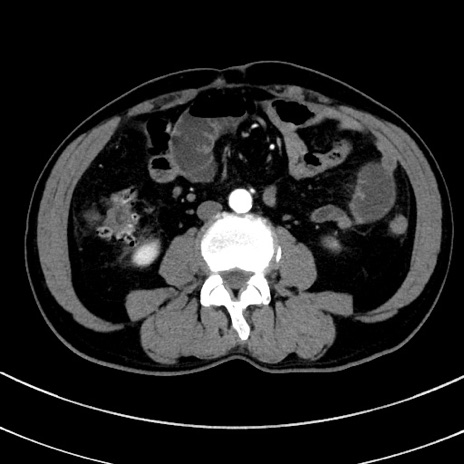

症例8(横断像)

冠状断像

【症例】 60歳代男性

【主訴】 黒色吐物

【現病歴】 4日前から嘔気自覚、2日前の朝食後にも嘔気あり、自分で手で嘔吐反射起こし嘔吐したところ血が混ざっていたため受診。

【既往歴】 5年前汎発性腹膜炎を伴う急性虫垂炎で手術、高血圧、前立腺肥大症、高脂血症

【身体所見】 腹部正中に手術癩痕あり 腹部平坦・軟圧痛なし膨満感あり

【データ】WBC 8400、CRP 4.54